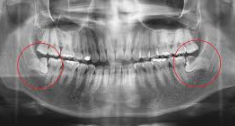

사람의 턱은 크기가 한정되어 있기 때문에 수용할 수 있는 치아의 갯수가 한정적입니다. 턱이 발달되고 큰 사람들은 사랑니가 자라나도 정상적으로 자라나 문제가 없을수도 있지만 사랑니가 자라는 대부분의 사람들은 수용할 수 있는 치아의 갯수가 초과되기 때문에 치아가 자라날 자리가 없어 잇몸을 비집고 자라거나 잇몸안에서 나오지 못하는 경우가 대부분 입니다.

그렇기 때문에 어금니 신경을 건들여 통증이 있고 좁은 잇몸을 비좁고 나오려고 하기 때문에 붓는 증상이 나타나게 됩니다.